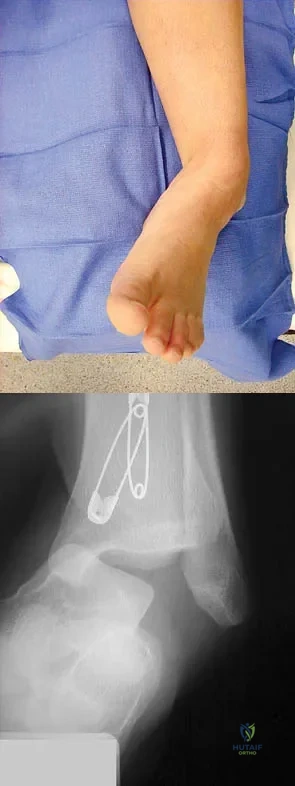

A full-term newborn has webbing at the knees, rigid clubfeet, a Buddha-like posture of the lower extremities, and no voluntary or involuntary muscle action at and below the knees. Radiographs of the spine and pelvis reveal an absence of the lumbar spine and sacrum. What maternal condition is associated with this diagnosis?

Explanation